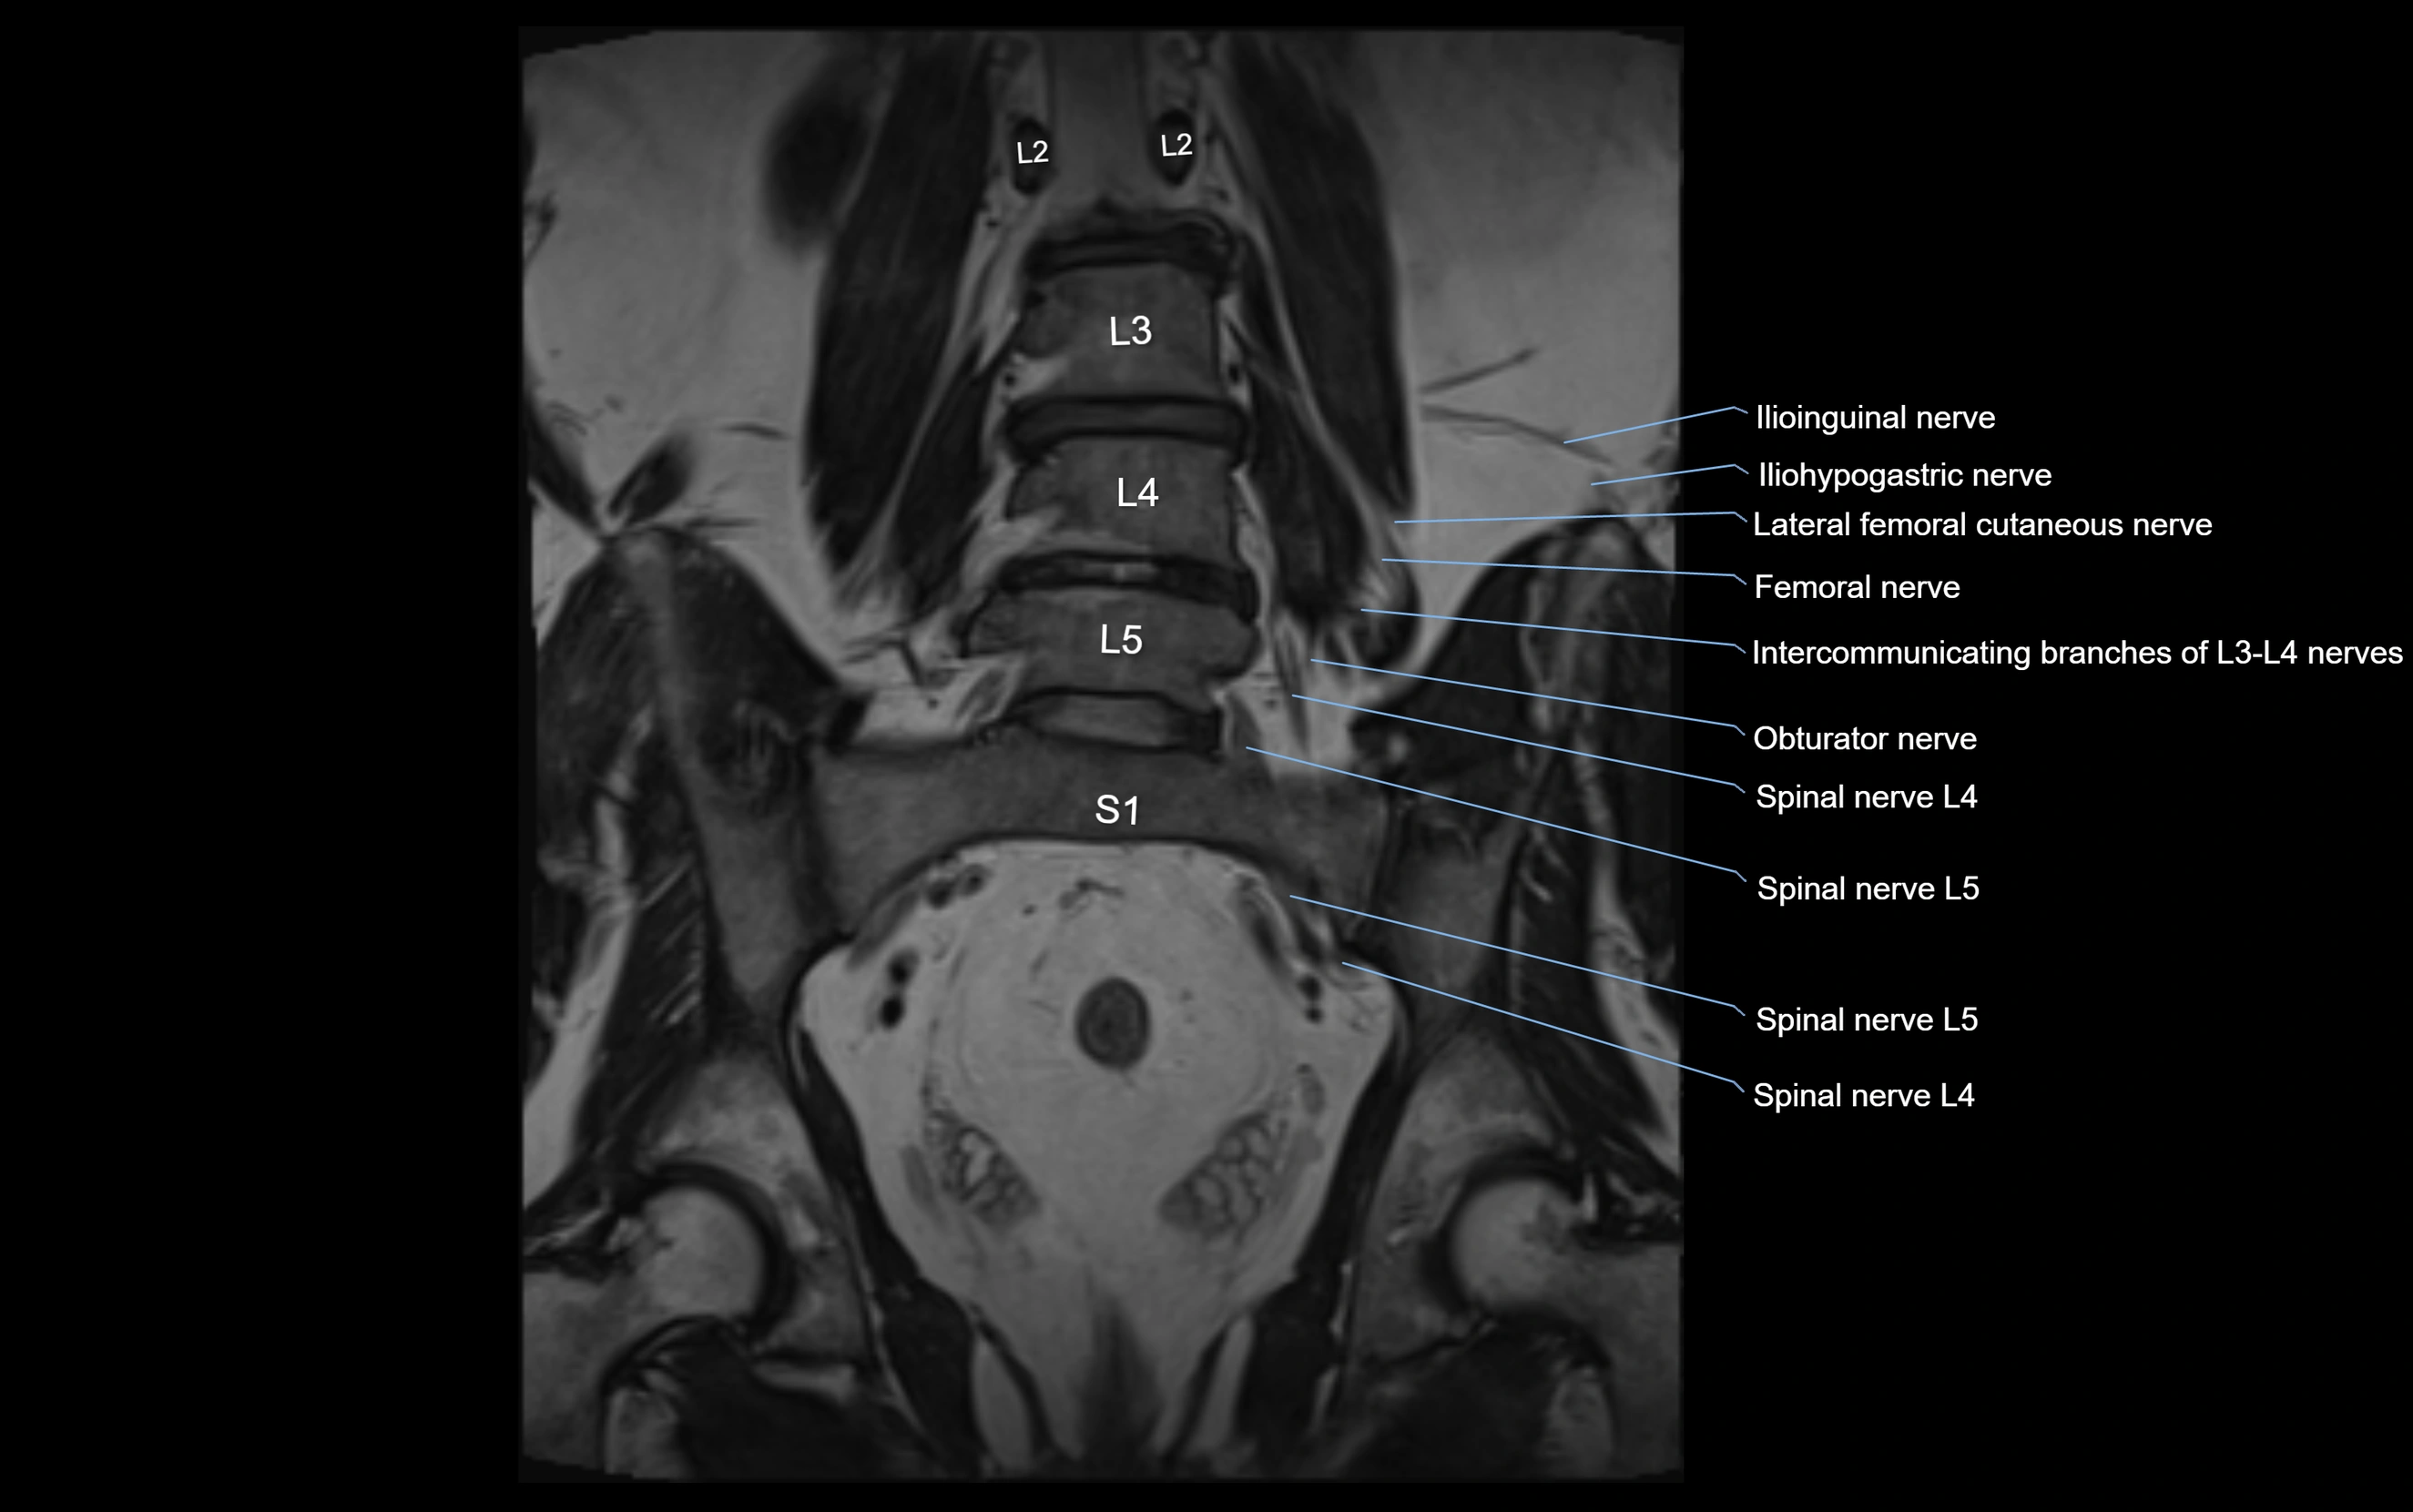

MRI image

image